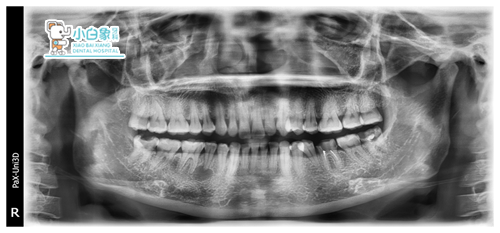

X线示:45根尖区类圆形暗影,边缘骨白线。36根管充填影像,欠填,尖端膨大。

诊断: 1.45根尖囊肿

2.36无髓牙